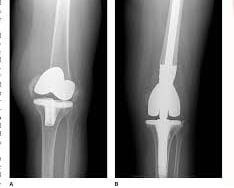

• Periprosthetic Fractures

Orthopaedic Trauma Surgeons are unique in that they specialize in complex injuries to bones, joints and soft tissues (like muscles, tendons and ligaments) throughout the entire body. Many orthopaedic specialists specialize in just one body part. Others may provide more general care but won’t treat more acute fractures, which are physically more difficult to fix. Orthopaedic trauma physicians, however, receive training in the field of orthopaedic surgery with a special focus on the treatment of fractured bones and joint realignment to promote the safe recovery and return of functionality to injured body parts. So, they often treat patients with multiple broken bones, compound fractures and fractures near a joint (like a hip or knee).Orthopaedic trauma surgeons are able to follow patients through all stages of recovery and enlist the help of other specialists, if needed, to treat complex cases. By maintaining open communication with all providers, they are able to ensure each patient receives the care needed to resume a full and active lifestyle.